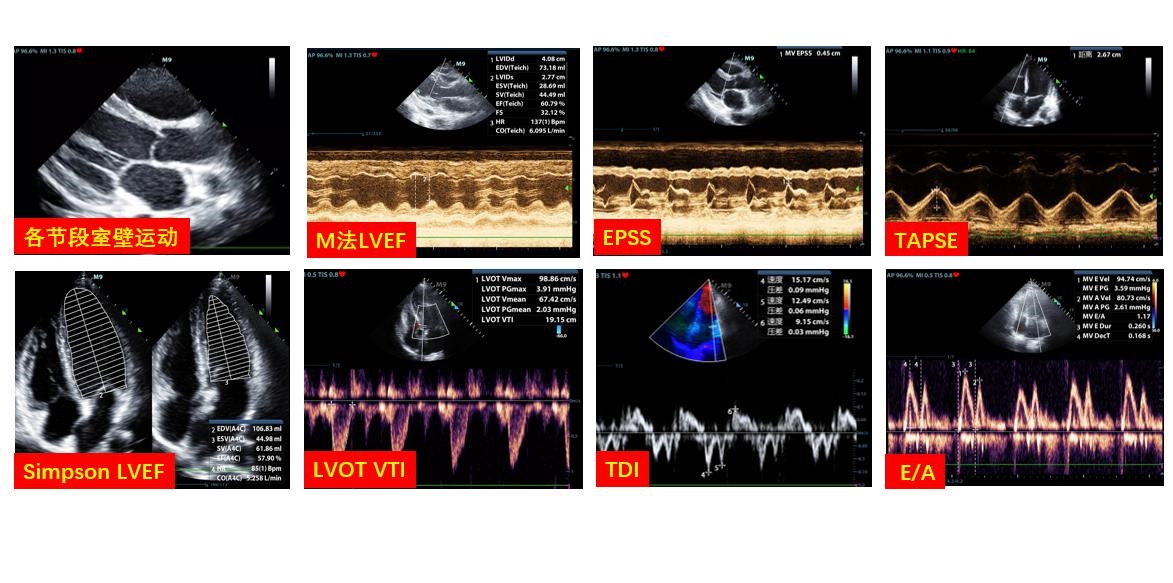

C、心室功能通过观察左右心室收缩协调性、其中无节段室壁运动异常者可通过胸骨旁左室长轴切面测量左室射血分数(left ventricular ejective fraction LVEF),存在室壁运动异常者可通过Simpson法测量LVEF,亦可通过左室流出道测量速度时间积分(Left ventricular outflow tract velocity time integral LVOT VTI)计算每博量及心排出量,测量速度时间积分变异率协助评估患者容量状态;三尖瓣环收缩位移(tricuspid annular plane systolic excusion TAPSE)、右心室面积法可用于评估右心室收缩功能(图 5)。

| LVEF:左室射血分数;EPSS:舒张期二尖瓣前叶最大开放点(E点)与室间隔左室面的最小距离;TAPSE:三尖瓣环平面收缩期位移值;LVOT:左室流出道;VTI:速度时间积分;TDI:组织多普勒;E/A:E峰速度与A峰速度比值 图 5 超声评估心脏收缩功能的各类指标 |

② VV-ECMO 床旁超声通过LVOT VTI和LVOT直径可快速测算出心排血量,从而制定匹配的ECMO流量;并结合血管超声和肺部超声共同对患者有效血容量进行调整,保证氧供;联合机械通气者监测右心舒张末内径,右心收缩功能、三尖瓣反流等肺动脉高压的超声证据,及时发现继发性肺动脉高压。VV-ECMO运行过程中,心脏超声探查发现合并心功能减退时,可更换至VA/VAV支持模式。

③ VA-ECMO 对患者心脏收缩、舒张功能进行评估和监测是确定理想ECMO流量和支持力度的前提。根据患者心脏功能来协助容量管理和流量调节贯穿于整个治疗过程中。

B、右心:右室大小、右心与左心比例可用于评估容量状态和右心后负荷即肺动脉压力情况,还可通过测量三尖瓣环收缩期运动幅度(TAPSE)半定量评估右心收缩功能,面积法计算右心射血分数、三尖瓣环组织多普勒测量其运动速度均可对右心收缩功能进行评估。

3.2 VA-ECMOVA-ECMO患者需每日使用床旁超声评估心脏功能,当心脏功能逐渐恢复并且心排量可以满足机体需求时,可考虑撤机[24]。心脏功能恢复的超声证据包括:无左室扩张状态、瓣膜反流减少,左室射血分数、左室流出道或主动脉速度时间积分、三尖瓣环收缩期运动幅度、三尖瓣环运动速度等左右心室收缩功能指标好转,但目前仍无上述各项指标的统一推荐值,需结合临床进行个性化动态评估,反复权衡ECMO获益和风险,才可选取最佳撤机时机。